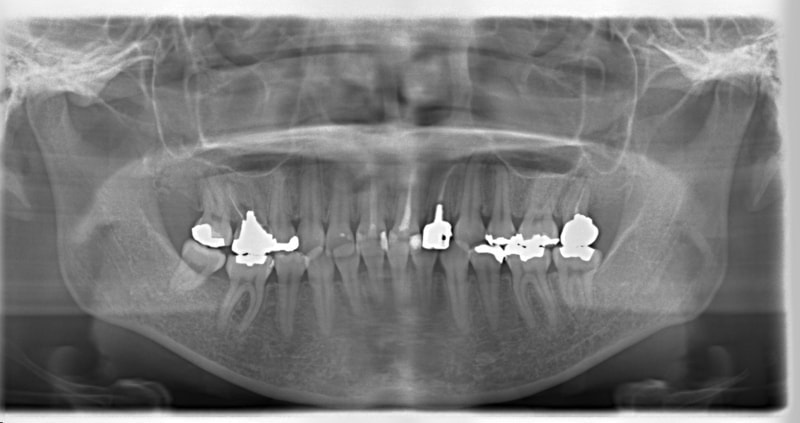

右下7番欠如歯(保存不可能歯につき抜歯)右下8番利用

治療前